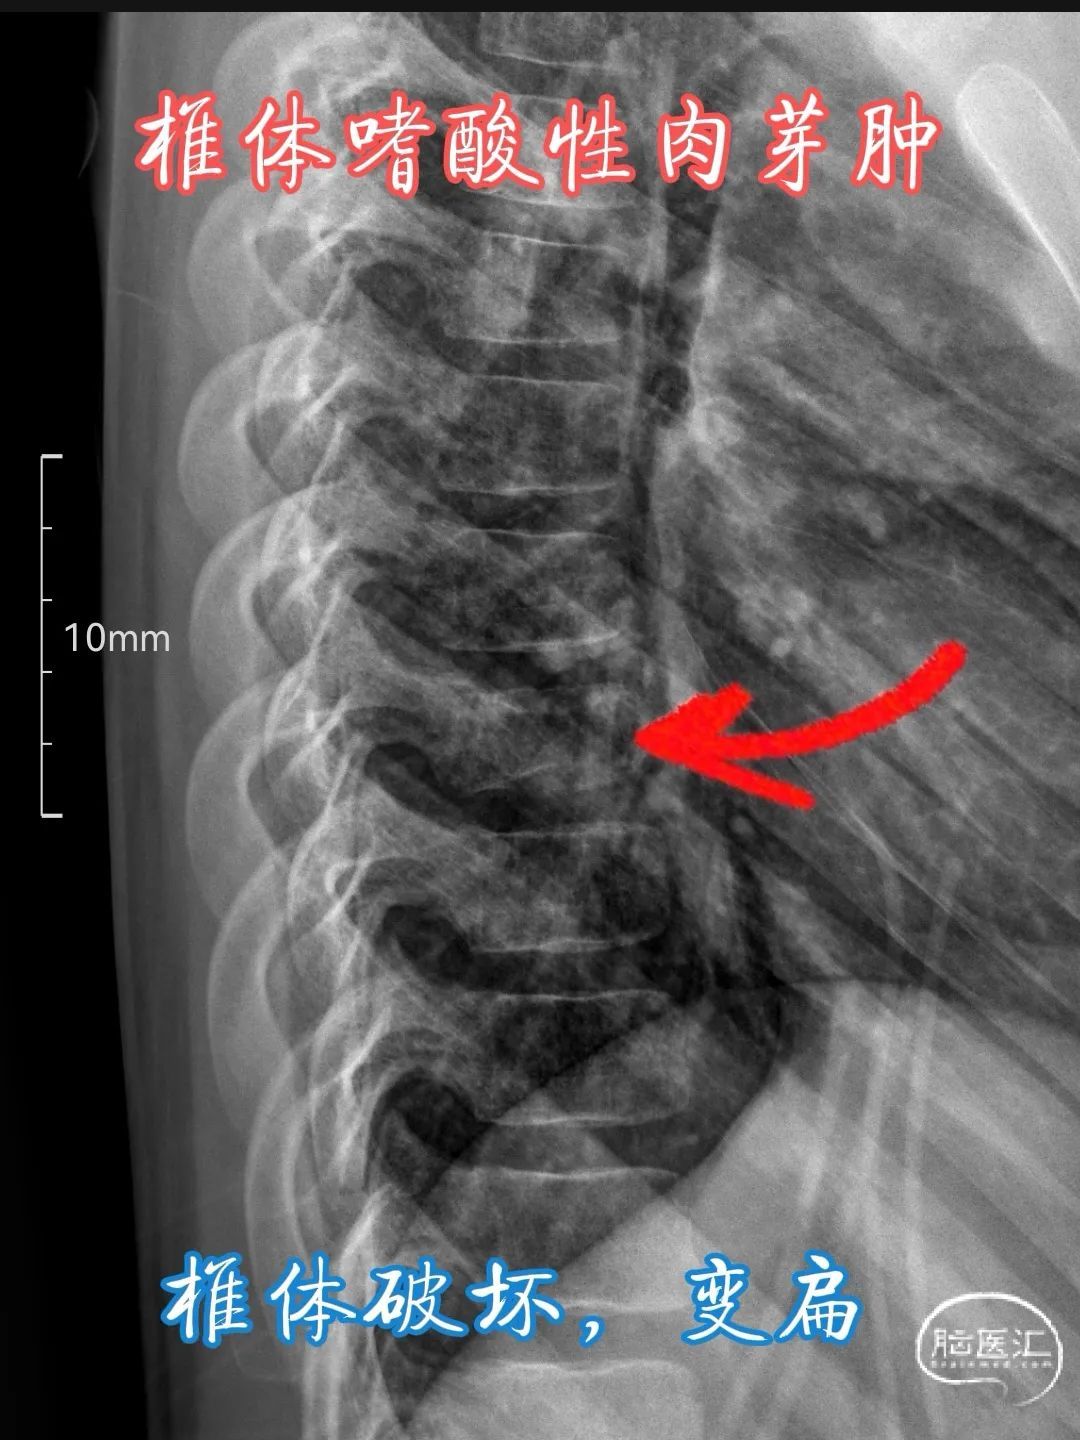

•X 线检查 :椎体嗜酸性肉芽肿在 X 线平片上常表现为椎体的溶骨性破坏,呈单房或多房的透亮影,边缘清晰或模糊,可伴有骨质疏松。典型的 X 线征象包括 “椎体平面”(vertebra plana),即椎体呈扁平状,上下缘平行,椎间隙保持正常,这是由于病变累及整个椎体,导致椎体被压缩变扁,多见于儿童患者。此外,还可能出现椎体楔形变、椎体崩裂等表现,病变周围软组织肿胀也不少见,可呈现为椎旁软组织密度影。